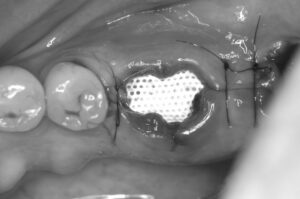

こんにちは。神奈川県藤沢市の菅井歯科医院藤沢です。 今日の午前中はインプラント埋入手術がありました。インプラント術前にソケットプリザベーション(Socket Preservation)という処置を併用した症例です。今日はこの「ソケットプリザベーション」というものについてご紹介したいと思います。 インプラントとは,人工歯根のことで,歯を失ってしまったところを補う有効な手段の一つです。 ですのでインプラントが用いられるのは当然,歯を失った後ということです。 歯を失う原因の多くは歯周病です。歯周病が悪くなった(=歯の周りの骨が溶けた)から抜歯をするわけですから,インプラントを埋入するときには骨が非常に少なくなってしまっていることもしばしばあります。 左の写真のように,インプラント埋入時に骨が足りないと,GBRという骨の再生手術を併用しなければなりません。当院では当然GBRも行っておりますが,術後に腫れたり内出血が起こったりしやすいので,避けられるものなら避けたいところです。 そこで,近年注目されているのが,ソケットプリザベーションという骨の温存手術です。 歯周病が悪化した歯を抜歯する際に,抜くだけでは大きな穴になってしまい,先ほどの写真のように骨が足りなくなってしまいますので 抜いたあとの穴に 骨に置換される材料を充填し その上を特殊な膜(d-PTFE非吸収性メンブレン)で被い,縫合します。 すると,4〜5ヶ月後には 骨の幅が完全に温存されているのがわかります! こうなれば,後はそのままインプラントを埋入するだけです。 ただ,シンプルに埋入するだけなので,患者さんの体の負担も少ない低侵襲なインプラント治療になりました。 縫合して終了です。 インプラント治療には様々な選択肢があります。また,技術は日々進化しています。治療の際には是非いろいろとご相談ください。